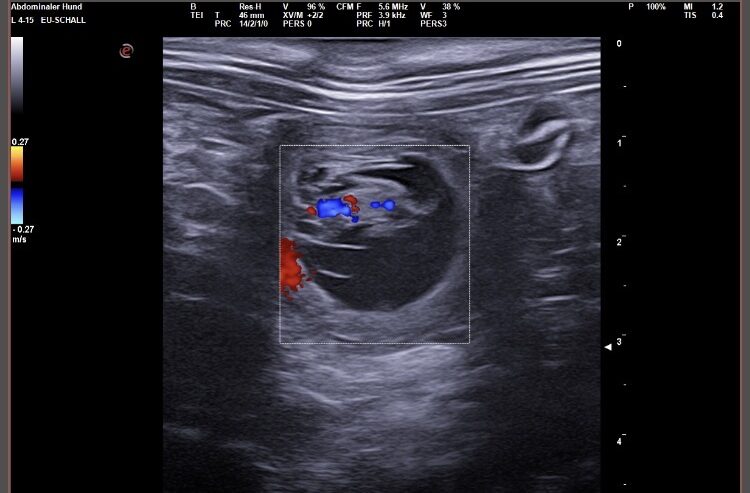

Wir waren erfolgreich und konnten Fruchtanlagen mit schlagenden Herzen sehen. Wir gehen zum aktuellen Zeitpunkt wieder von einem größeren Wurf aus. Daykos und Dorias Rendevouz war also sehr vielversprechend!

Hier zeigen wir euch einige der kleinen gefüllten Fruchtblasen mit Inhalt und schlagenden Herzen. Da wir kurz vor Ostern mit der Geburt rechnen, nennen wir sie „Ostereier“ 🙂